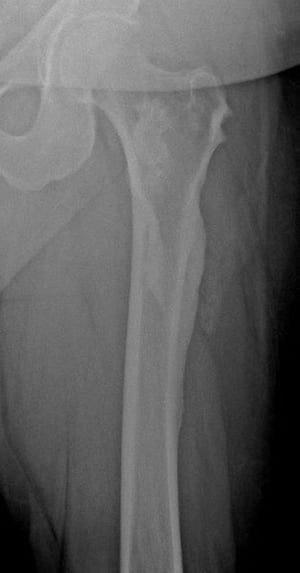

このX線写真には,42歳の患者の大腿骨近位部および骨盤に生じたメロレオストーシスが写っている。

Image courtesy of Michael J. Joyce, MD, and David M.Joyce, MD.